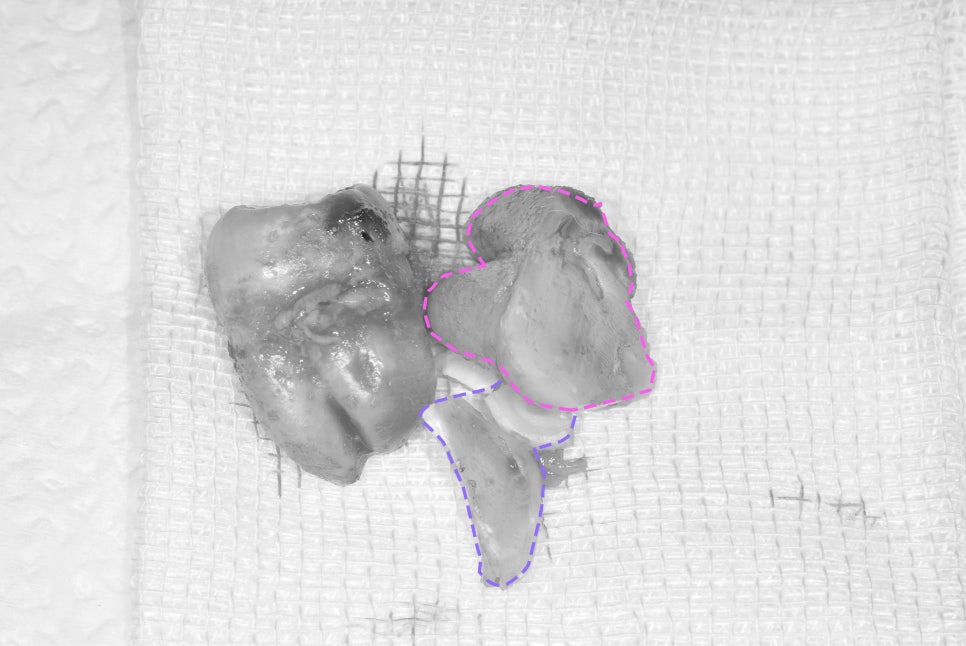

아래 사진을 보면

두 조각으로 나눠서 뽑은 것을 볼 수 있네요^^

치관과 치근을

따로 분리해서 뽑는

치료 계획을 수립하고 있습니다.